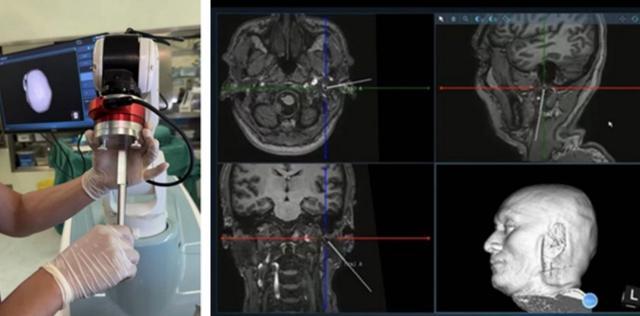

“面神经走行深、解剖结构复杂,周围毗邻重要血管神经,传统操作对经验依赖较强,风险控制难度较大。”杨靓教授介绍,“通过机器人导航与三维影像重建,我们实现了穿刺路径的精准规划与实时引导,使操作更加安全、稳定、可控。”

本次手术在局部麻醉下完成,患者全程清醒、耐受良好。术中通过高分辨率影像重建三维模型,精准规划路径,避开颈内动脉等重要结构,在机器人实时引导下将穿刺针准确送达面神经关键靶点——茎乳孔区。经电生理验证定位后,实施脉冲射频治疗。

依托机器人系统的高精度控制能力,手术实现了“路径可规划、操作可量化、风险可控制”,显著提升复杂解剖区域治疗的安全性,同时大幅缩短手术时间,降低围手术期风险,体现出明显的技术壁垒和平台优势。